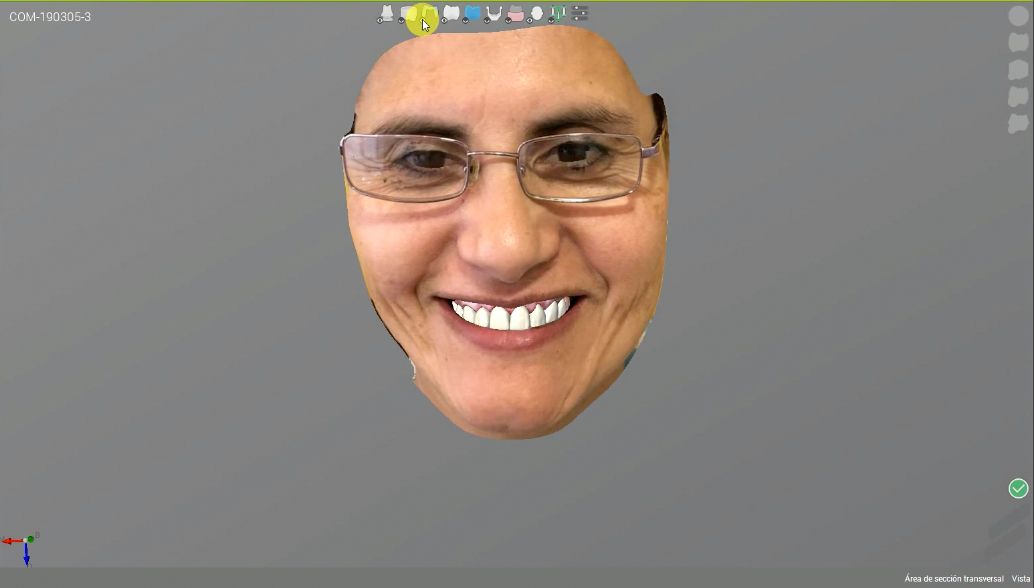

After a further intraoral scan, a new smile was designed using Straumann CARES® Visual. A 3D model printed with the Straumann P30 3D printer was used for the digital wax-up. Pictures were taken to register all the details needed for the final design of the restorations.

STL files of the digital wax-up, teeth preps, and the patient’s picture were uploaded to the Straumann CARES® Visual software, and crowns were designed. After 25 minutes, all the crowns were sent to be milled with the Straumann C series milling machine. On completion of the milling process, all the crowns were placed for a final fit check (Figs. 9-13).

The fit was confirmed, and only minor adjustments were needed at the contact points. The crowns were removed from the patient’s mouth and polished by hand using Ivoclar Vivadent OptraFine (Figs. 14 & 15).

All the crowns were cemented using IPS Ceramic Etching Gel according to the Ivoclar Multilink protocol (Figs. 16-21).

Treatment outcome

The patient was very happy with the functional and esthetic result, as well as the short treatment period. She finally received her new smile in a much shorter time than expected, and this had been a key driver in her decision to accept our treatment plan.